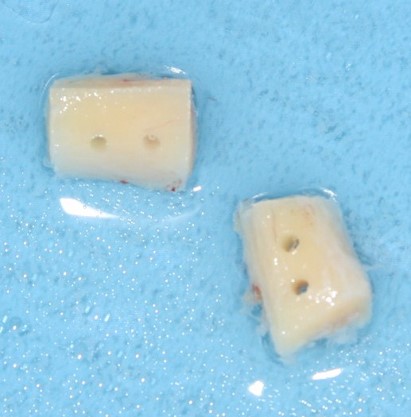

Да-да, угадали. Это т. н. «базальные импланты», которые активно рекламируются в качестве альтернативы остеопластическим операциям. Они удалены из-за подвижности и неспособности обеспечить качественную опору протетической конструкции. И, должен заметить, это бывает даже слишком часто, чтобы быть просто случайностью. В общем-то, эта картинка вполне себе дает представление, как нужно поступать с подобными методиками и к чему приводит желание сделать все «быстро, качественно и недорого».